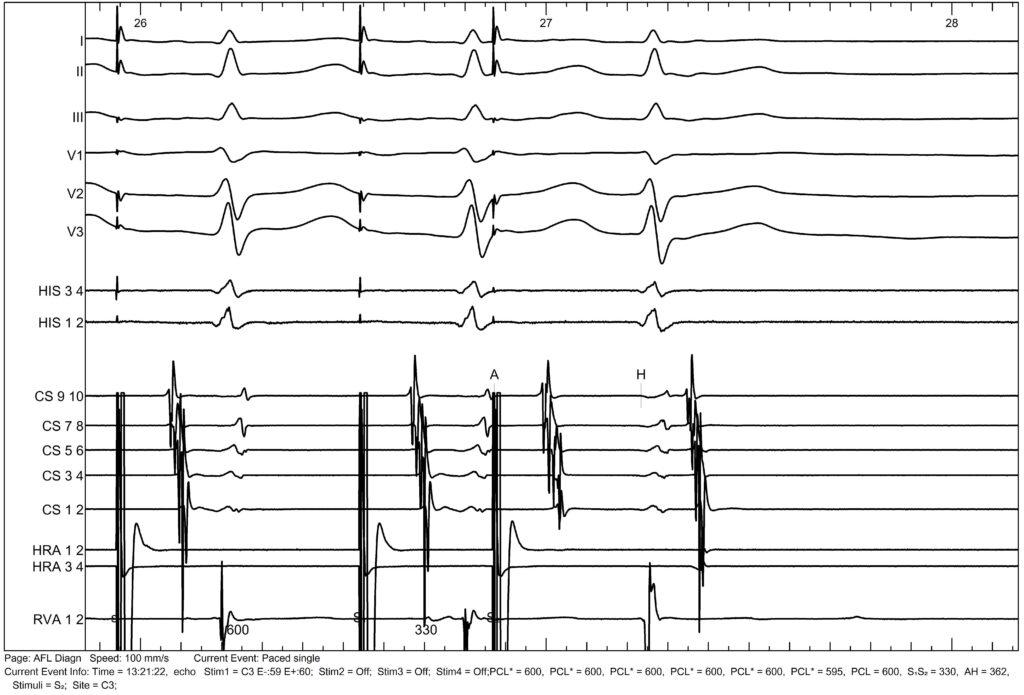

We repeated the study in 2025 and again observed a jump, also associated with an echo.